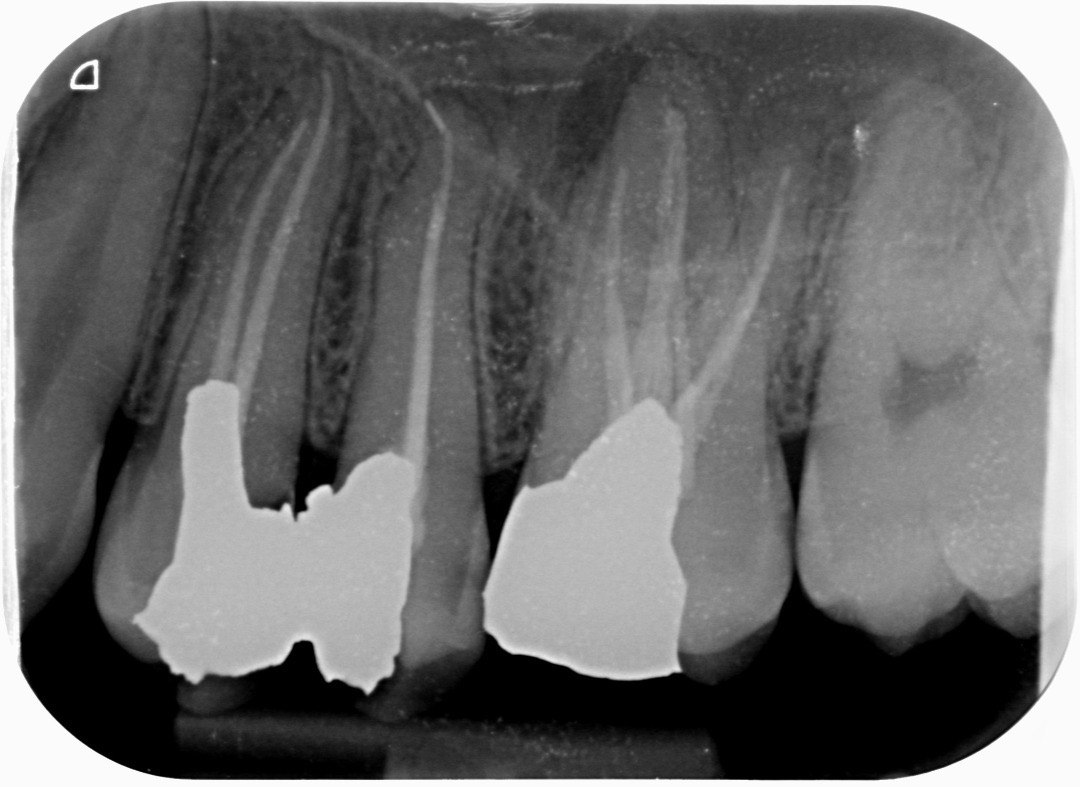

3. What is the caries level on the distal surface of the tooth # 3.6?

6: What is the caries level of mesial of the tooth # 3.6?

7: What is the caries level of Distal of the tooth # 3.6?

16. What are the caries level in mesial and distal surfaces of the tooth # 4.6 respectively?

17. What is the Caries level on distal surface of the tooth # 3.5?